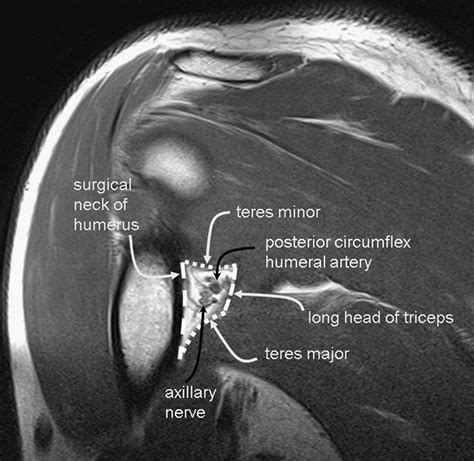

To understand why Quadrilateral Space Syndrome occurs, one must first visualize the anatomical boundaries of the space itself. The quadrilateral space is an anatomical tunnel located in the posterior shoulder, bounded by several key structures that define its shape and function. If these boundaries become restricted, the structures passing through them face significant pressure.

• Superior Boundary: The teres minor muscle.

• Inferior Boundary: The teres major muscle.

• Medial Boundary: The long head of the triceps brachii muscle.

• Lateral Boundary: The surgical neck of the humerus.

The neurovascular bundle consisting of the axillary nerve and the posterior circumflex humeral artery traverses this space to innervate the deltoid and teres minor muscles. When fibrous bands, hypertrophied muscles, or trauma occur in this area, the nerve becomes impinged, leading to the characteristic symptoms of the syndrome.